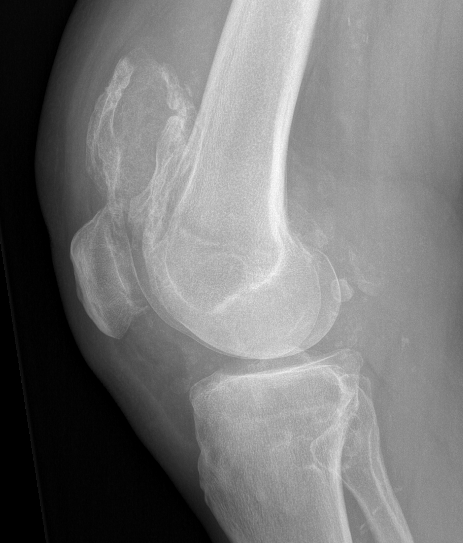

X-ray

Demonstrate calcified lesions / synovial osteochondromatosis

Synovial chondromatosis

Synovial osteochondromatosis